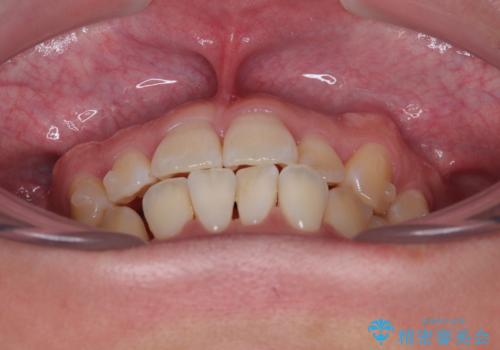

- 前歯の反対咬合などを気にして来院された患者様です。

ワイヤー矯正、マウスピース矯正どちらでも対応可能であったので、ご本人の希望によりインビザラインにて矯正治療を行うこととしました。

マウスピース矯正は、ワイヤー矯正と違い、とにかく自己管理が非常に重要となります。

毎日の装着時間をしっかりと守ってくださり、1年強の短期間で、あっという間に治療を終えることができました。